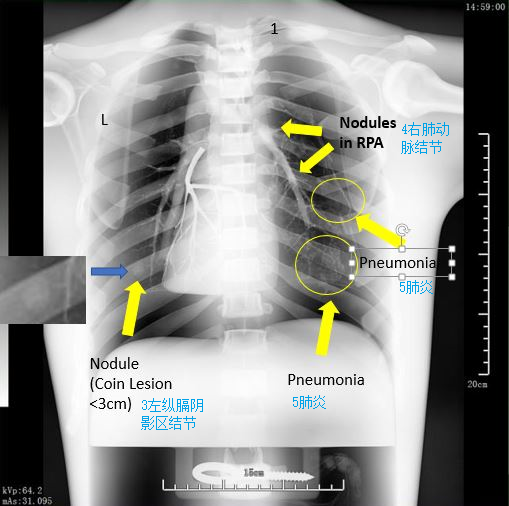

1和2肺部軟組織陰影 3肺炎斑塊

2. 5種標(biāo)準(zhǔn)病理學(xué)形態(tài)模擬

1)第一左肋尖端上2個(gè)連續(xù)的直徑0.5cm結(jié)節(jié)

2)疊加在左肺下葉大血管上的直徑0.6cm結(jié)節(jié)

3)左縱膈陰影區(qū)直徑1.5cm結(jié)節(jié)

4)混合在右肺動(dòng)脈0.6cm結(jié)節(jié)

5)右下肺葉肺炎模擬